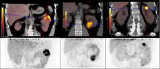

研究: Ga-68 FAPI-RGD在癌症成像中具有广阔的应用前景

根据最近的一项研究,中国的研究人员开发了一种PET放射性示踪剂,它可以与癌症患者的两个确定的诊断靶点结合,并表明这种“双受体靶向”能力可能比当前的方法更具优势。